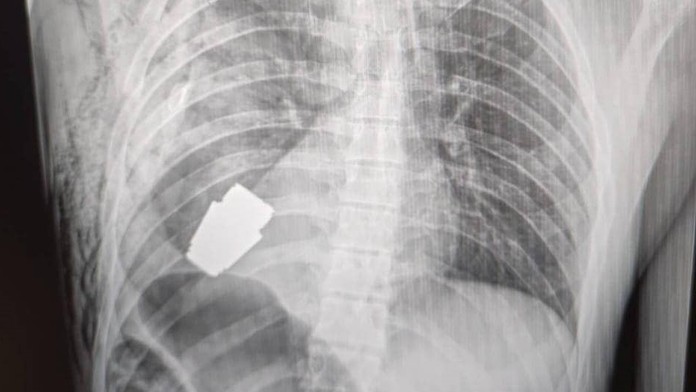

Chirurgovia odstránili zbraň nachádzajúcu sa tesne pod srdcom raneného vojaka, pričom dvaja ženisti zaisťovali, aby operácia prebehla bezpečne, uviedla námestníčka ukrajinského ministra obrany Hanna Maľarová. Na svojej stránke na Facebooku zverejnila aj röntgenovú snímku granátu vo vnútri vojakovho tela.

„Vojenskí lekári urobili operáciu na odstránenie granátu VOG, ktorý nevybuchol, z tela vojaka,“ napísala v príspevku na Facebooku Maľarová.

Zákrok prebehol bez použitia elektrokoagulácie – bežnej metódy na obmedzenie krvácania počas operácie –, pretože "granát mohol vybuchnúť v ktorejkoľvek chvíli", uviedla Maľarová.

Jedna fotografia zachytávala chirurga, ako výbušnú zbraň, granát, drží po operácii v ruke.

Vojaka potom poslali na ďalšiu rehabilitáciu a zotavenie. Heraščenko napísal vo štvrtok ráno na sociálnej sieti Telegram aktualizované informácie: „Spod srdca vybrali nevybuchnutú časť granátu. Granát neexplodoval, ale bol stále výbušný.“